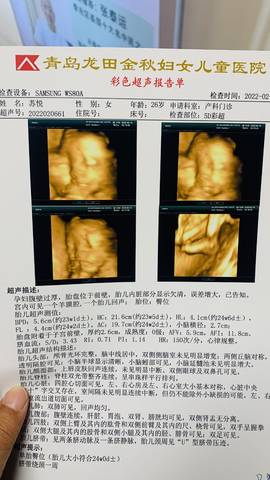

16号做的四维。医生说没啥问题。大家帮忙看看。希望宝宝健康。乖一点。让我老婆少受点罪????????????

如果你这个四维彩超没什么大的问题的话,那就没有关系了,你可以厄做其他检查看啦。